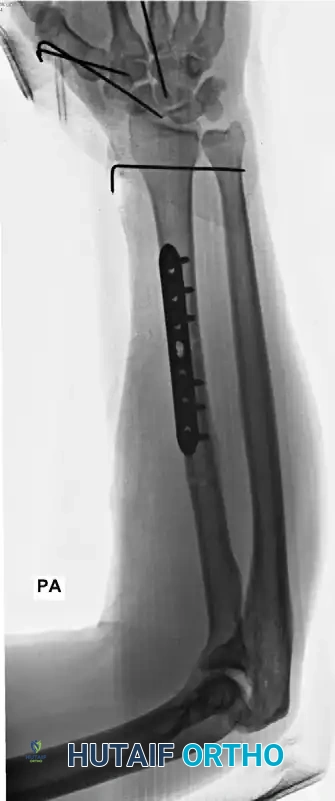

Galeazzi Fracture-Dislocations

A Galeazzi injury involves a fracture of the distal third of the radial shaft coupled with a dislocation or subluxation of the DRUJ. These are highly unstable injuries that mandate operative intervention in adults.

The radius must be anatomically reduced and rigidly fixed, typically utilizing a dynamic compression plate (DCP) or a locking compression plate (LCP). Following radial fixation, the DRUJ must be assessed for stability throughout the forearm arc of motion. If the DRUJ remains unstable, it is often pinned in supination using parallel Kirschner wires.